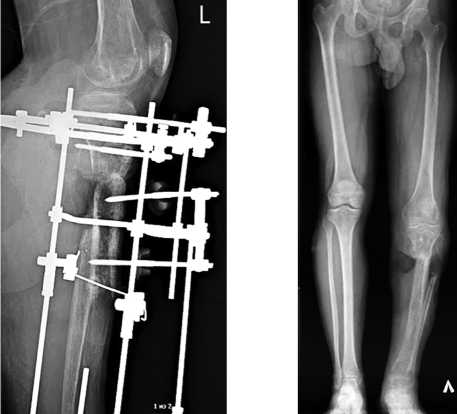

После стабилизации состояния и заживления ран на левой голени (рис. 1) через 72 дня после ранения провели операцию: внеочаговый чрескостный компрессионно-дистракционный остеосинтез (ВЧКДО) по Илизарову левой голени, остеотомия дистального отломка левой большеберцовой кости. Дефект большеберцовой кости — 15 см. На 79-е сутки после ранения начали перемещение фрагмента с целью формирования регенерата и замещения дефекта. На 164-е сутки после ранения (85 суток после остеотомии) для коррекции положения и направления перемещения фрагмента выполнили перемонтаж аппарата Илизарова на левой голени. Продолжили перемещение фрагмента дистального отломка большеберцовой кости (рис. 2).

Рис. 1. Фото и рентгенограмма левой голени перед реконструктивной операцией

Рис. 2. Фото и рентгенограмма левой голени в процессе транспорта кости

На 261-е сутки после ранения (182-е сутки после остеотомии) отметили контакт фрагмента и проксимального отломка через зону инвагинации (рис. 3). В целях обеспечения контакта проксимального отломка и перемещаемого фрагмента дистального отломка на 262-е сутки после ранения (183-и сутки после остеотомии) выполнили резекции зоны инвагинации и костно-хрящевого комплекса на торце проксимального отломка и перемещаемого фрагмента, открытую репозицию отломков, перемонтаж аппарата Илизарова. Достигнут контакт торцевых частей проксимального отломка и перемещаемого фрагмента (рис. 4). В последующем проводили компрессию между проксимальным отломком и фрагментом, «воспитание регенерата» методом «аккордеона».

Сращение между проксимальным отломком и фрагментом, а также созревание регенерата отмечены на 493-и сутки, выполнили демонтаж аппарата Илизарова (рис. 5). Продолжили реабилитацию в течение 60 суток (рис. 6).

Рис. 3. Фото и рентгенограмма левой голени при сближении проксимального отломка и перемещаемого фрагмента (инвагинация)

Рис. 5. Телерентгенограмма нижних конечностей пациента после окончания лечения

Рис. 6. Внешний вид пациента в положении опоры на левой ноге и в положении сгибания в левом коленном суставе

Рис. 4. Рентгенограмма левой голени после операции устранения инвагинации, резекции зоны ложного сустава, репозиции отломков, перемонтажа аппарата Илизарова

Общий срок лечения составил 553 суток, ИВФ — 43,7 сут./см, анатомический результат по шкале ASAMI — удовлетворительный, функциональный результат по шкале ASAMI — хороший.